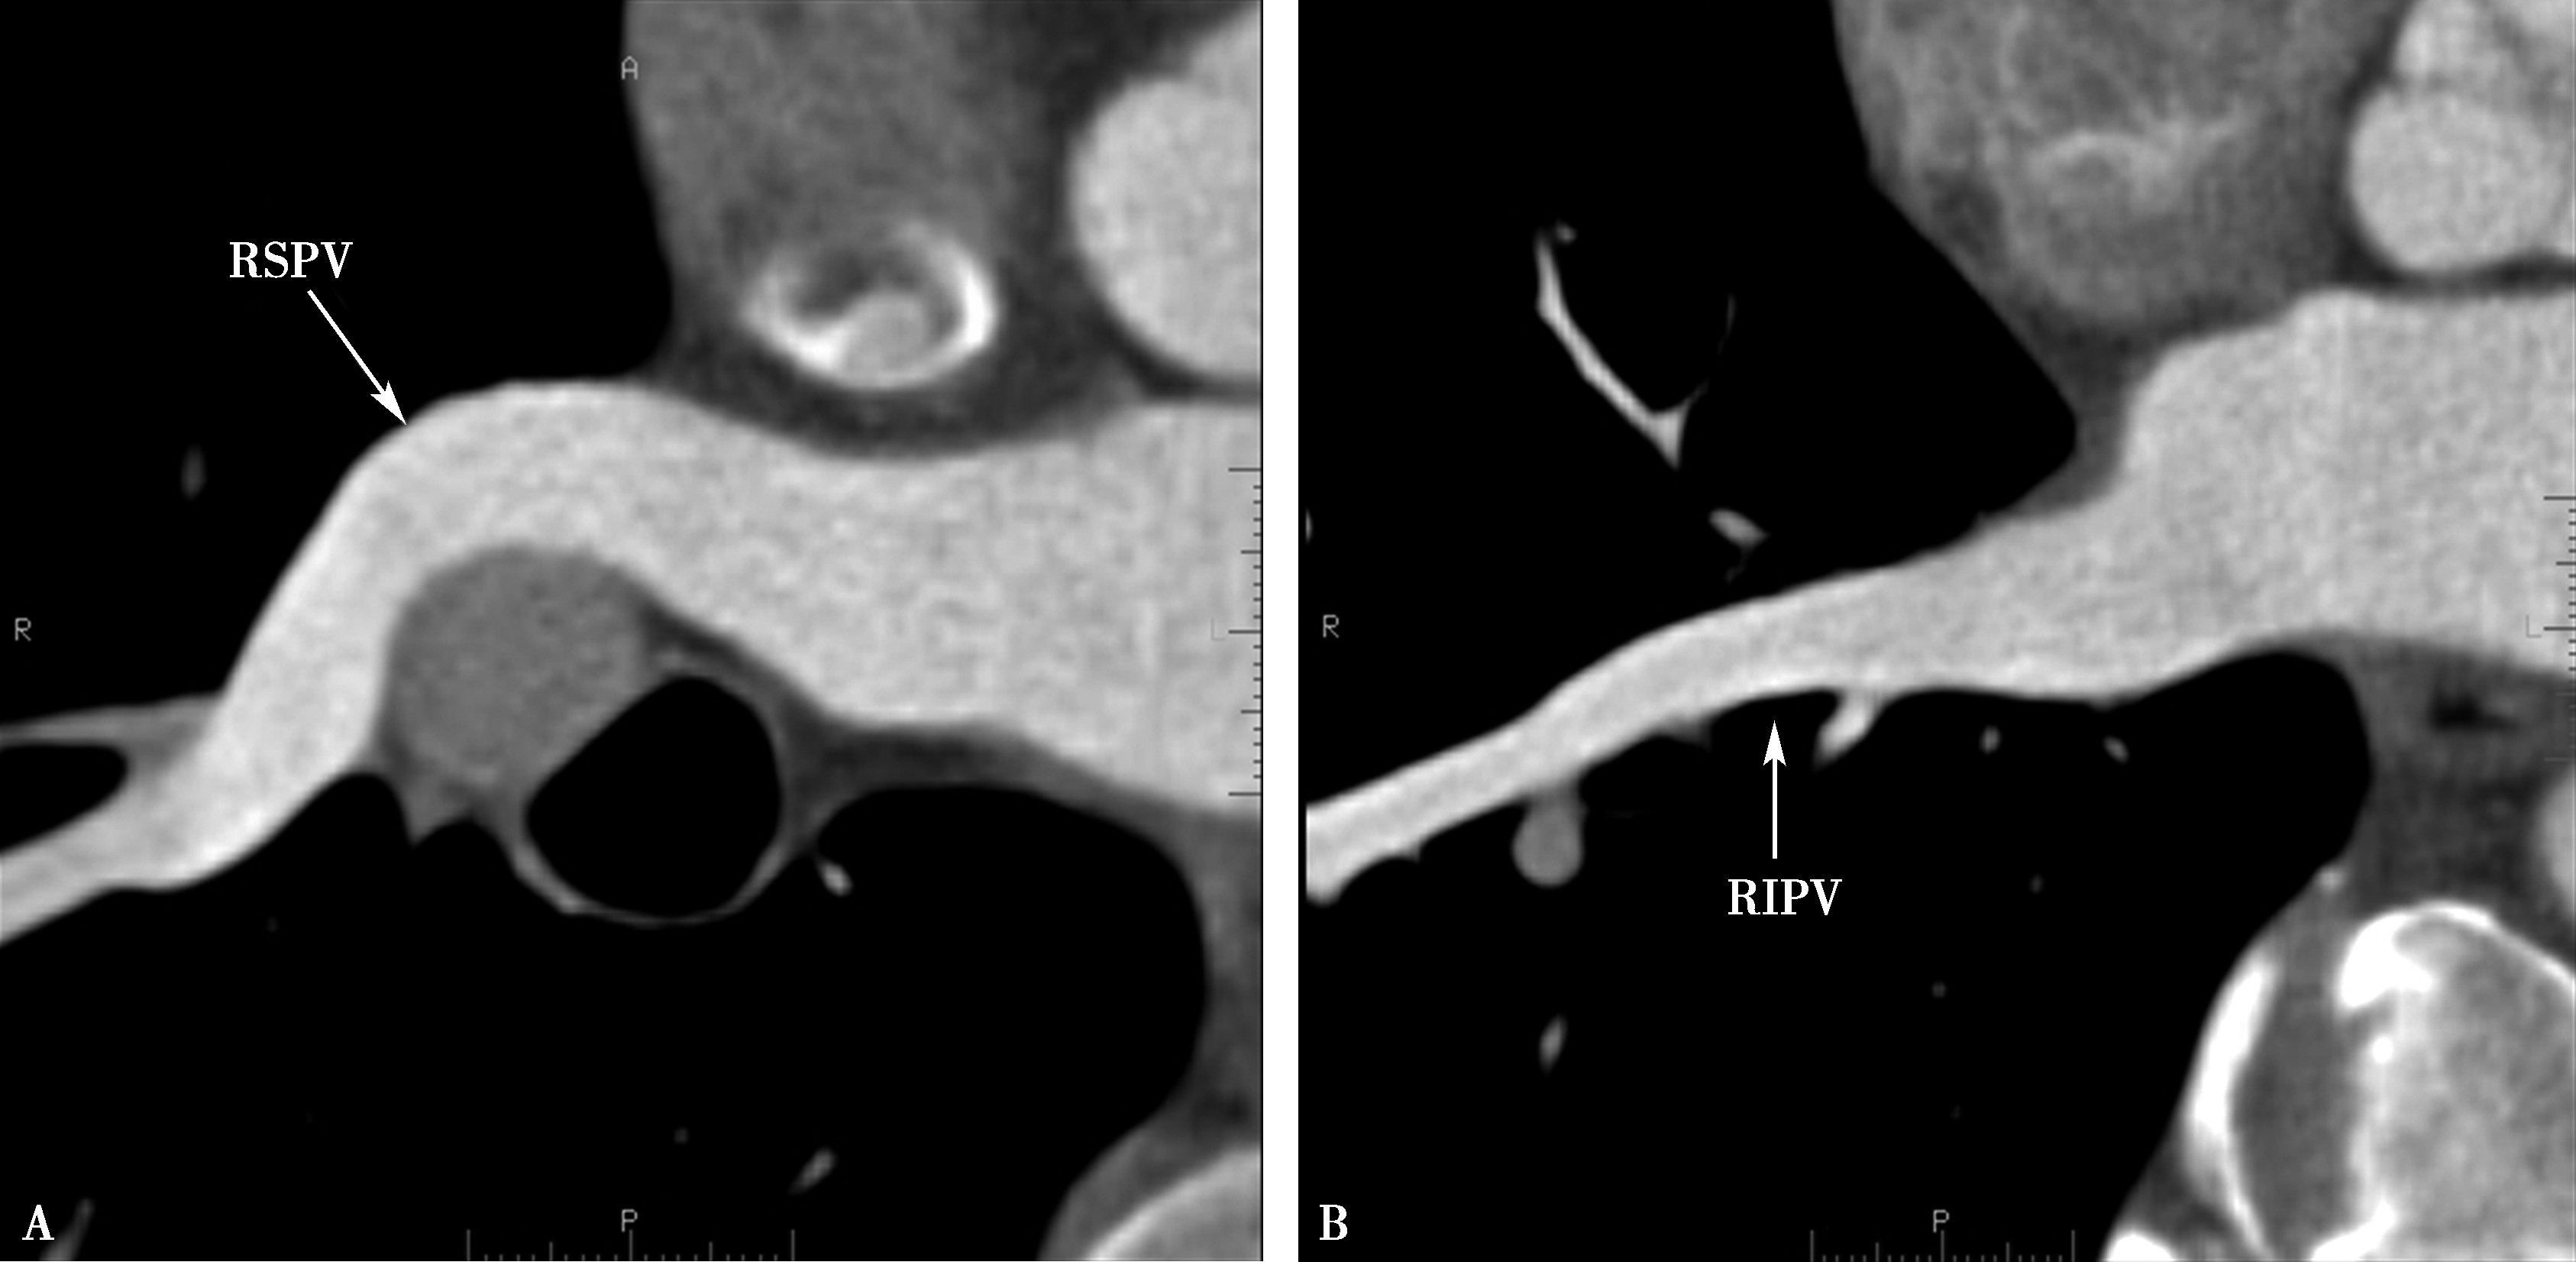

(二)肺静脉解剖

3.最大密度投影(MIP)(图8-2-12)

图8-2-12 肺静脉最大密度投影(MIP)

A.冠状位;B.冠状位;C.右前斜位,右肺静脉;D.左前斜位,左肺静脉。RSPV:右上肺静脉;RIPV:右下肺静脉;LSPV:左上肺静脉;LIPV:左下肺静脉;LA:左心房;LV:左心室

4.容积再现(VR)(图8-2-13)

图8-2-13 左心房-肺静脉容积再现(VR)

A.冠状位;B.背面观;C.冠状位适度LAO;D.背面观适度LAO。RSPV:右上肺静脉;RIPV:右下肺静脉;LSPV:左上肺静脉;LIPV:左下肺静脉;LA:左心房